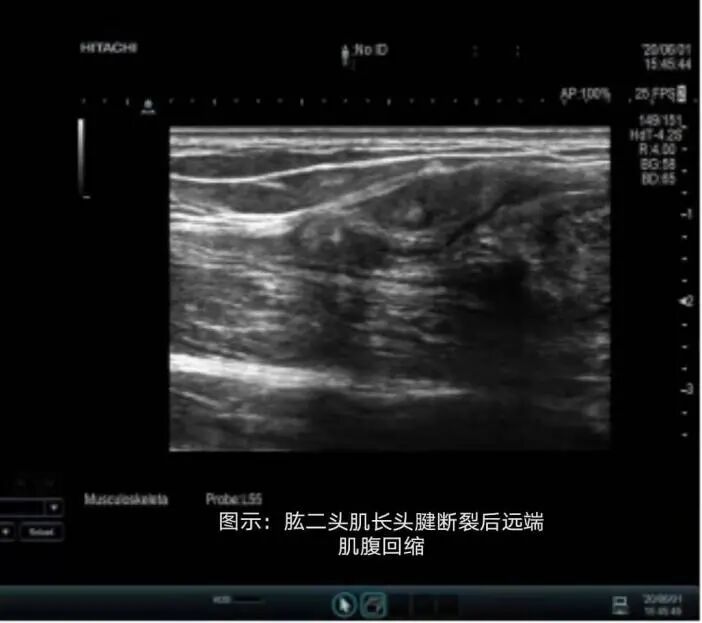

肱二頭肌長頭肌腱和肌腹連接處是斷裂的好發(fā)部位,在強力屈肘或搬運重物時,牽拉力超過負荷時易發(fā)生。斷裂后,肌腹常向下回縮,形成外觀上能與肌肉男相似的隆起,又稱為“大力水手征”。

如何甄別“肌肉”還是病態(tài)的“大力水手征”呢?這里我們強烈推薦一項檢查——肌骨超聲。肌骨超聲能清晰地顯示肱二頭肌長頭肌腱斷裂的斷端,對于診斷此類型的肌骨病變具有很大的優(yōu)勢。